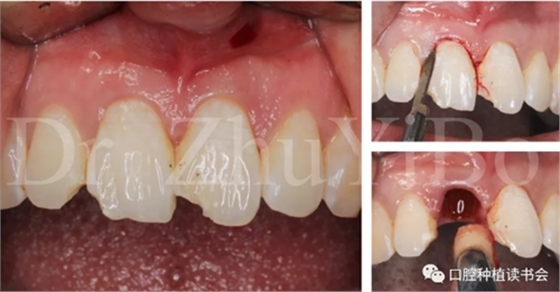

一位年輕女性患者,右上中切牙外傷冠根折2日。

臨床檢查發(fā)現:右上中切牙冠根折,斷面位于齦緣下4到5個毫米。左上中切牙及右上側切牙,切角缺損,牙髓活力正常(圖7)。

圖7 外傷導致11冠根折

4.2.1微創(chuàng)拔出牙齒,挺出根尖(圖9)

圖9 斷裂牙根需用微創(chuàng)器械拔除

4.2.2 拔牙窩沖洗,定點,備洞(圖10)。

圖10 種植窩洞相對于天然牙長軸偏向腭側